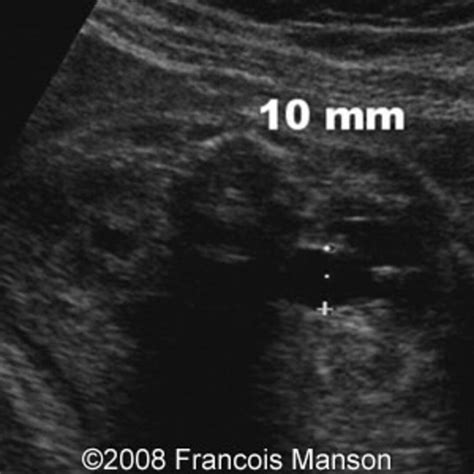

Pyelectasis of the fetus is typically diagnosed during routine prenatal ultrasound examinations. The diagnosis is based on the measurement of the anteroposterior diameter (APD) of the renal pelvis. The severity of pyelectasis is categorized as follows:

Severity APD Measurement (mm)

Mild 4-7

Moderate 7-10

Severe Greater than 10